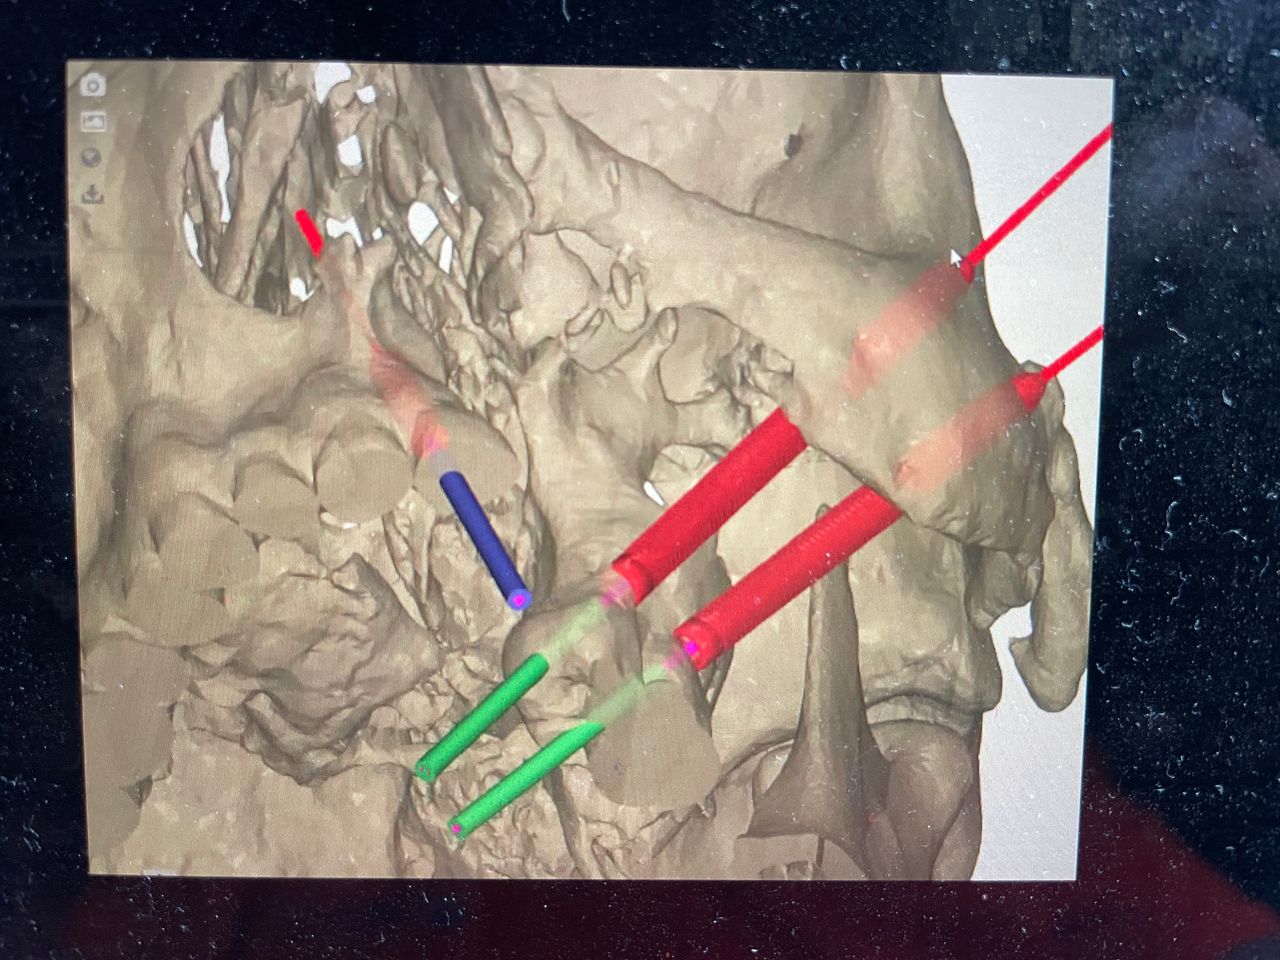

I have experience in oral surgery procedures such as: simple extractions, extraction of impacted teeth and third molars, biopsies, frenectomies, dental implants, zygomatic implants, juxta-osseous implants, and guided bone and tissue regeneration.

- Implantes cigomáticos